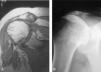

En la rotura del manguito de los rotadores hay factores de mal pronóstico14 que condicionan la estrategia quirúrgica y el resultado funcional. Estos factores incluyen la edad, el contexto social y profesional, la limitación activa de la antepulsión (inferior a 120o) y de la rotación externa (inferior a 30o), un período de rehabilitación funcional e infiltraciones superior a 6 meses, una valoración en la escala de Constant inferior a 40 puntos, la disminución de la distancia acromiohumeral (inferior a 7 mm) y la artrosis o la degeneración grasa muscular de los músculos infraespinoso y supraespinoso (fig. 7).

Figura 7. Resonancia magnética del músculo supraespinoso. (A) Proyección oblicua sagital de músculo normal. (B) Proyección oblicua sagital de músculo atrófico.